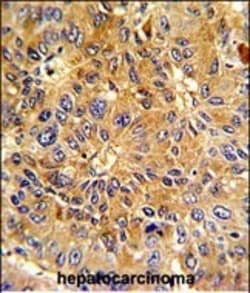

Invitrogen™ Cyclin A2 Polyclonal Antibody

Cyclin A2 Polyclonal Antibody for Western Blot, ICC/IF, IHC (P), Flow

| Applications | Flow Cytometry, Immunohistochemistry (Paraffin), Western Blot, Immunocytochemistry |